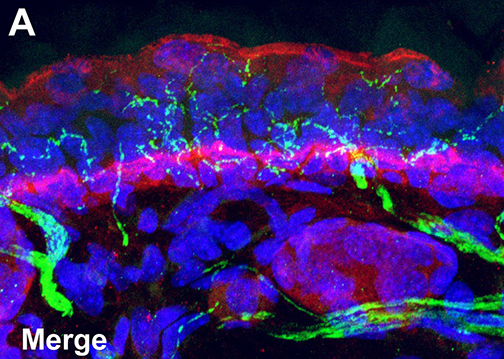

LSU Health New Orleans Develops New Human Cell Line to Study Blinding Eye Disorders

Under the direction of Boyd Professor Nicolas Bazan, MD, PhD, scientists at LSU Health New Orleans Neuroscience Center of Excellence have developed a new, experimental human cell line from retinal pigment epithelial cells. Called ABC, these cells so closely resemble and retain the properties of native retinal pigment epithelial (RPE) cells, the research team has shown that they are a reliable cell system to study retinal degenerative diseases. More